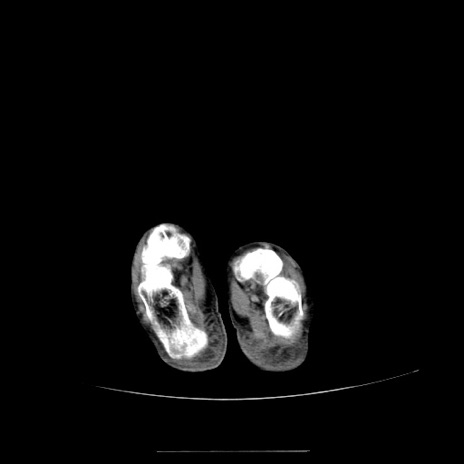

症例5(横断像)

【症例】70歳代女性

【主訴】お腹が張る

【現病歴】1週間くらい前から腹部膨満の自覚あり。昨日夜から増悪したため、本日救急外来受診。

【身体所見】意識清明、BT 36.5℃、BP 165/106mmHg、HR 80bpm、SpO2 98%、腹部:膨満、軟、自発痛・圧痛なし、触診にて不快感あり、腸蠕動音:減弱

【データ】WBC 12600、CRP 1.04